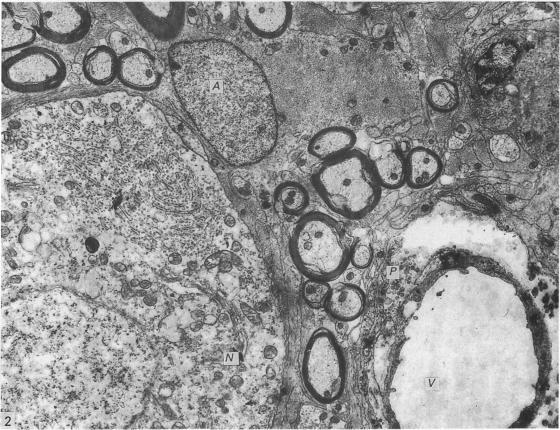

The possible secretory function of astrocytes in the marginal nuclei of the avian spinal cord.

J Anat. 1989 Aug;165:19-27.